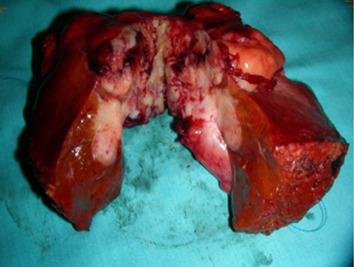

Cholecystectomy and segmental hepatectomy of segments S4b and S5 were performed. An 8 cm, friable gallbladder mass had grown outward and involved the liver (Fig. 3). Pathologically, the tumor was a sarcomatoid carcinoma in Stage III (Fig. 4). The surgical margin was free of vessel or cystic duct invasion. The tumor had an adenocarcinoma component with some glandular structures and showed positive staining for cytokeratin (AE1/AE3) and a sarcoma component with spindle cells staining positively for vimentin.

Figure 3. An 8 cm friable mass extending outward from the gallbladder and involving the liver. |